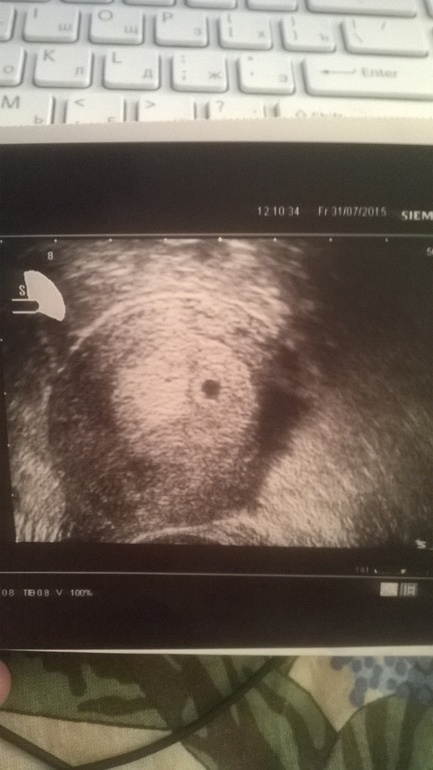

У нас получилось! Я беременна!Девчонки, добрый день! Принимайте в свое сообщество во второй раз) С первым малышом просто читала и ничего не писала, о чем очень сожалею. Во второй раз буду все записывать и сравнивать с первой беременностью. Была сегодня на узи) Мою бусинку нашли!!!! По месячным сегодня 5,1 и по зачатию 2,6 (20 ДПО). По узи все тютелька в тютельку сошлось) Плодное яйцо 7 мм). Прилагаю фото сегодняшнего тестика и первое фото моей крошечки